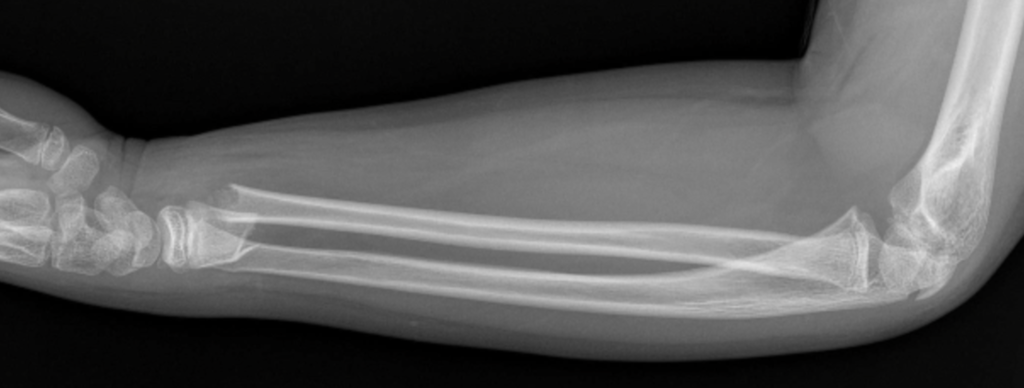

Fratura em “galho verde”